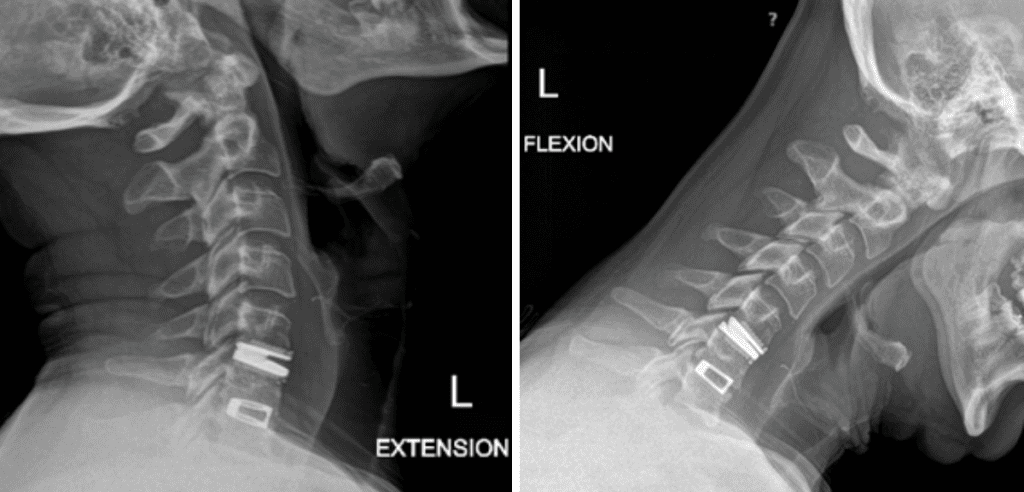

He had no neurologic deficits on exam, and therefore was started on a trial of multidisciplinary and multimodal conservative management. This included non-opioid pharmacologic regiment, lifestyle modification, physiotherapy, chiropractic, and epidural steroid injection. Despite these conservative measures, his symptoms remained severe and debilitating, and therefore surgical options were discussed. He underwent an uneventful C5-6 anterior artificial disc replacement. Postoperatively, his neck and radicular arm pain had fully resolved. Imaging demonstrated maintained physiologic flexion and extension of the cervical spine (Figure 2). This motion-preserving surgery reduces the adjacent degeneration process, and the need for further surgeries down the line.

Figure 2: Postoperative dynamic xrays; note the differences in range of motions between the artificial disc at C5-6 and the previous fusion at C6-7.